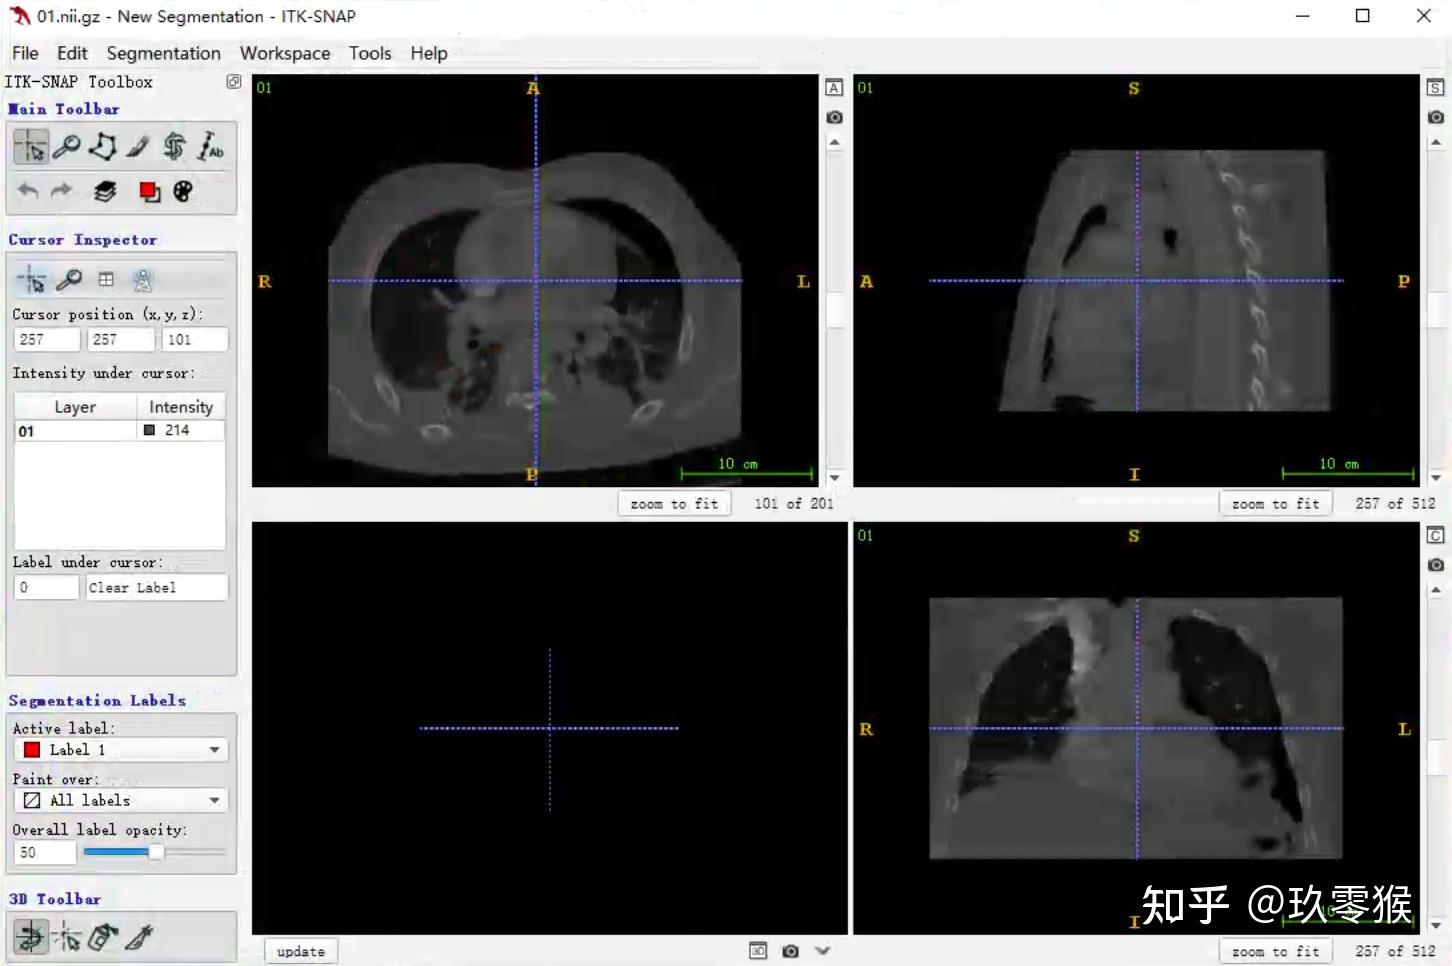

2、载入相应的分割图数据( nii.gz文件)

Segmentation - > Open Segmentation -> Browse... -> Next

3、3D可视化

左键可以选装3D图像

右键加滚轮可以缩放3D图像

2、载入相应的分割图数据( nii.gz文件)

Segmentation - > Open Segmentation -> Browse... -> Next

3、3D可视化

左键可以选装3D图像

右键加滚轮可以缩放3D图像